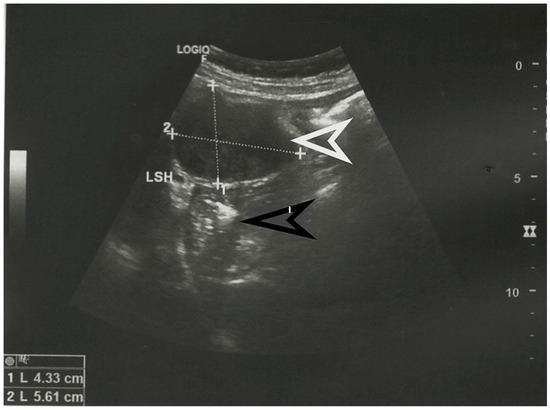

Abdominal ultrasound showing the presence of an iso-hypoechoic tumoral formation, marked with a white arrow, in a 56-year-old patient without any abdominal symptoms. The stomach is indicated with a black arrow and the left hepatic lobe is marked LSH. The dimensions of the tumor in cm are specified at the bottom left. No other pathological changes were identified by ultrasound. Submucosal tumors, also known as mesenchymal tumors, are a group of tumors that contain spindle-shaped cells [1]. They are classified histopathologically as a gastrointestinal stromal tumor (GIST), tumors originating from smooth muscle tissue, which, in turn, includes leiomyomas, leiomyosarcomas, and tumors originating from nervous tissue. The latter category includes schwannomas, granular cell tumors, and neurofibromas [2]. Gastric schwannoma is a tumor that originates from the nerve plexus of the intestinal wall [3]. More specifically, this tumor originates from Schwann cell sheaths and represents 0.2% of all gastric tumors [4]. Most commonly, gastric schwannoma originates from the Auerbach plexus, located in the smooth muscle layer of the gastric wall, and less commonly from the Meissner submucosal plexus. As it grows, the tumor pushes the nerve to the periphery, with no change in neuronal function [5]. This tumor is most often benign and is more common in women between the ages of 50–60 [4,6]. We present the case of a 56-year-old asymptomatic patient who was diagnosed, following a routine ultrasound examination, with an abdominal tumor. The ultrasound appearance of the tumor is presented in Figure 1.